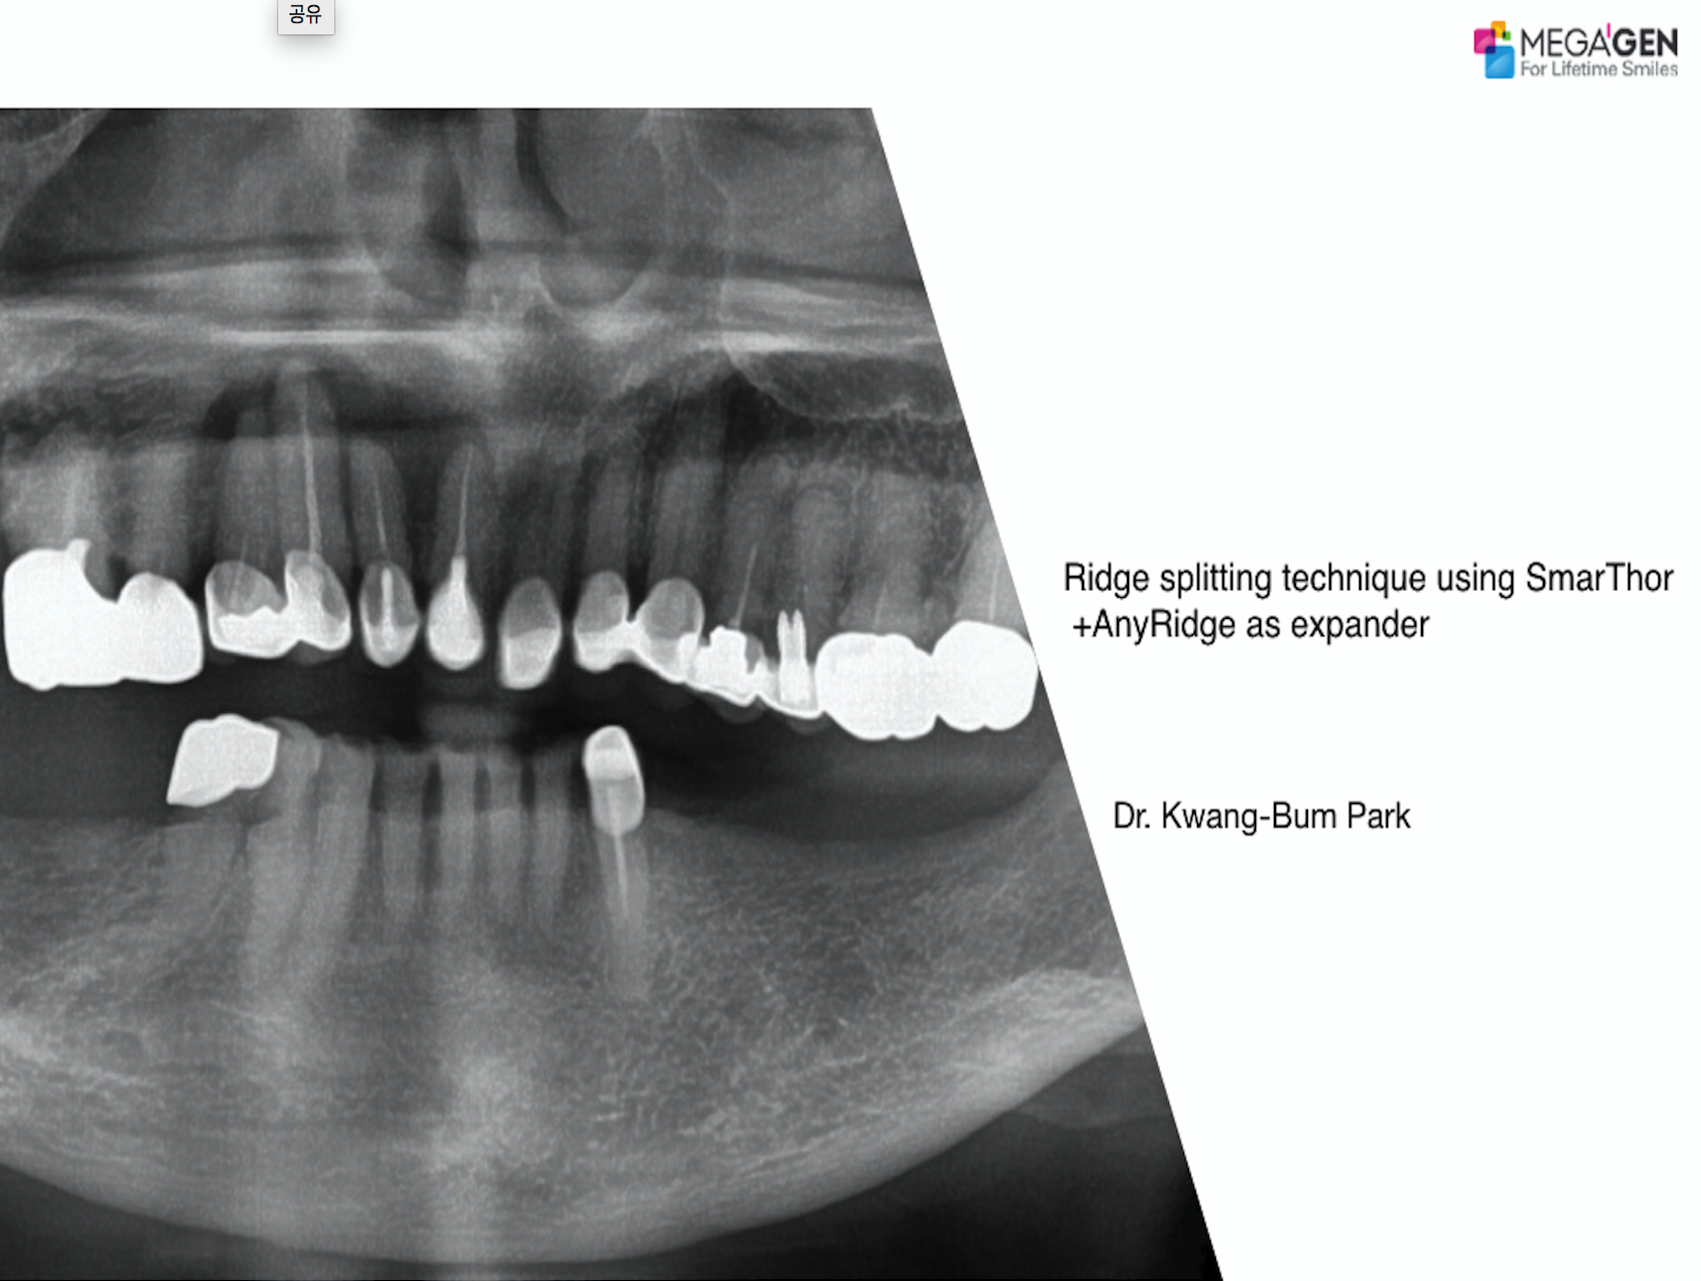

Dr. Hyung Jun Kim,Edentulous,Maxillary Anterior,Maxillary Posterior,Mandibular Anterior,Mandibular Posterior,#12,#22,#32,#45,#14,#24,#36,#46,#15,#25,#37,#47,#17,#27,#41,Immediate Placement,AnyRidge,Full-mouth implants,Full mouth rehabilitation,Octa abutment,Long-term clinical case,Biological stability